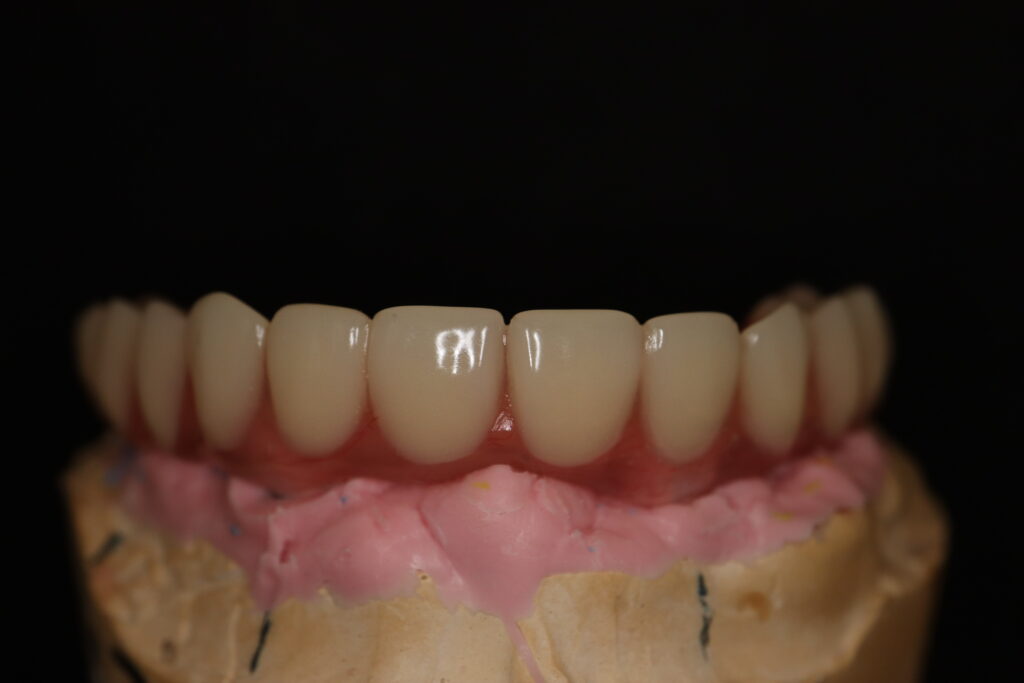

Процесс работы

После установки 6ти имплантантов Megagen Anyone, было принято решение зафиксировать металлоакриловый протез протез на 4 имплантата.

2 крайних имплантата, установленных в бугры, были ушиты с целью дальнейшего приживления. При постоянном протезирование протез будет зафиксирован на 6ти имплантатах.

Спустя 7 дней на верхней челюсти зафиксирован металлоакриловый протез из 12 зубов с опорой на 4 дентальные имплантата.

протез